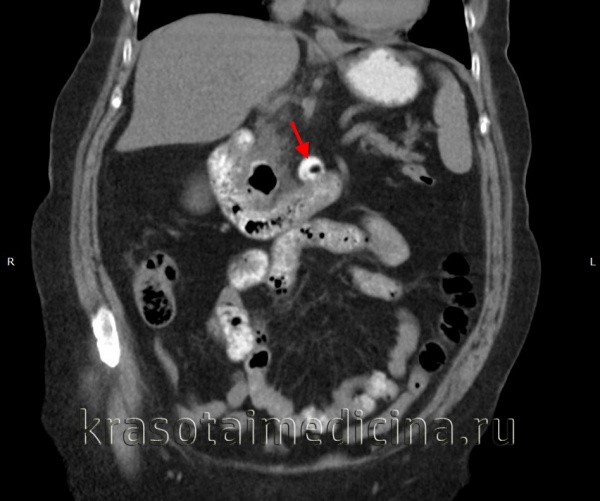

КТ ОБП. Дивертикул горизонтальной части 12-перстной кишки, заполненный частично контрастом, частично – газом.